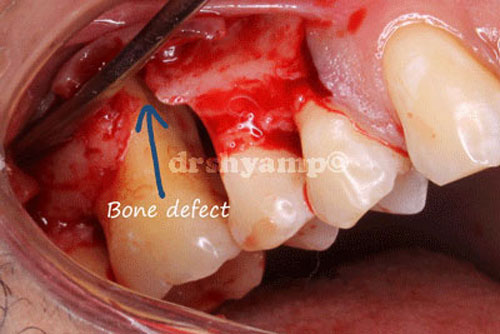

Bone grafting